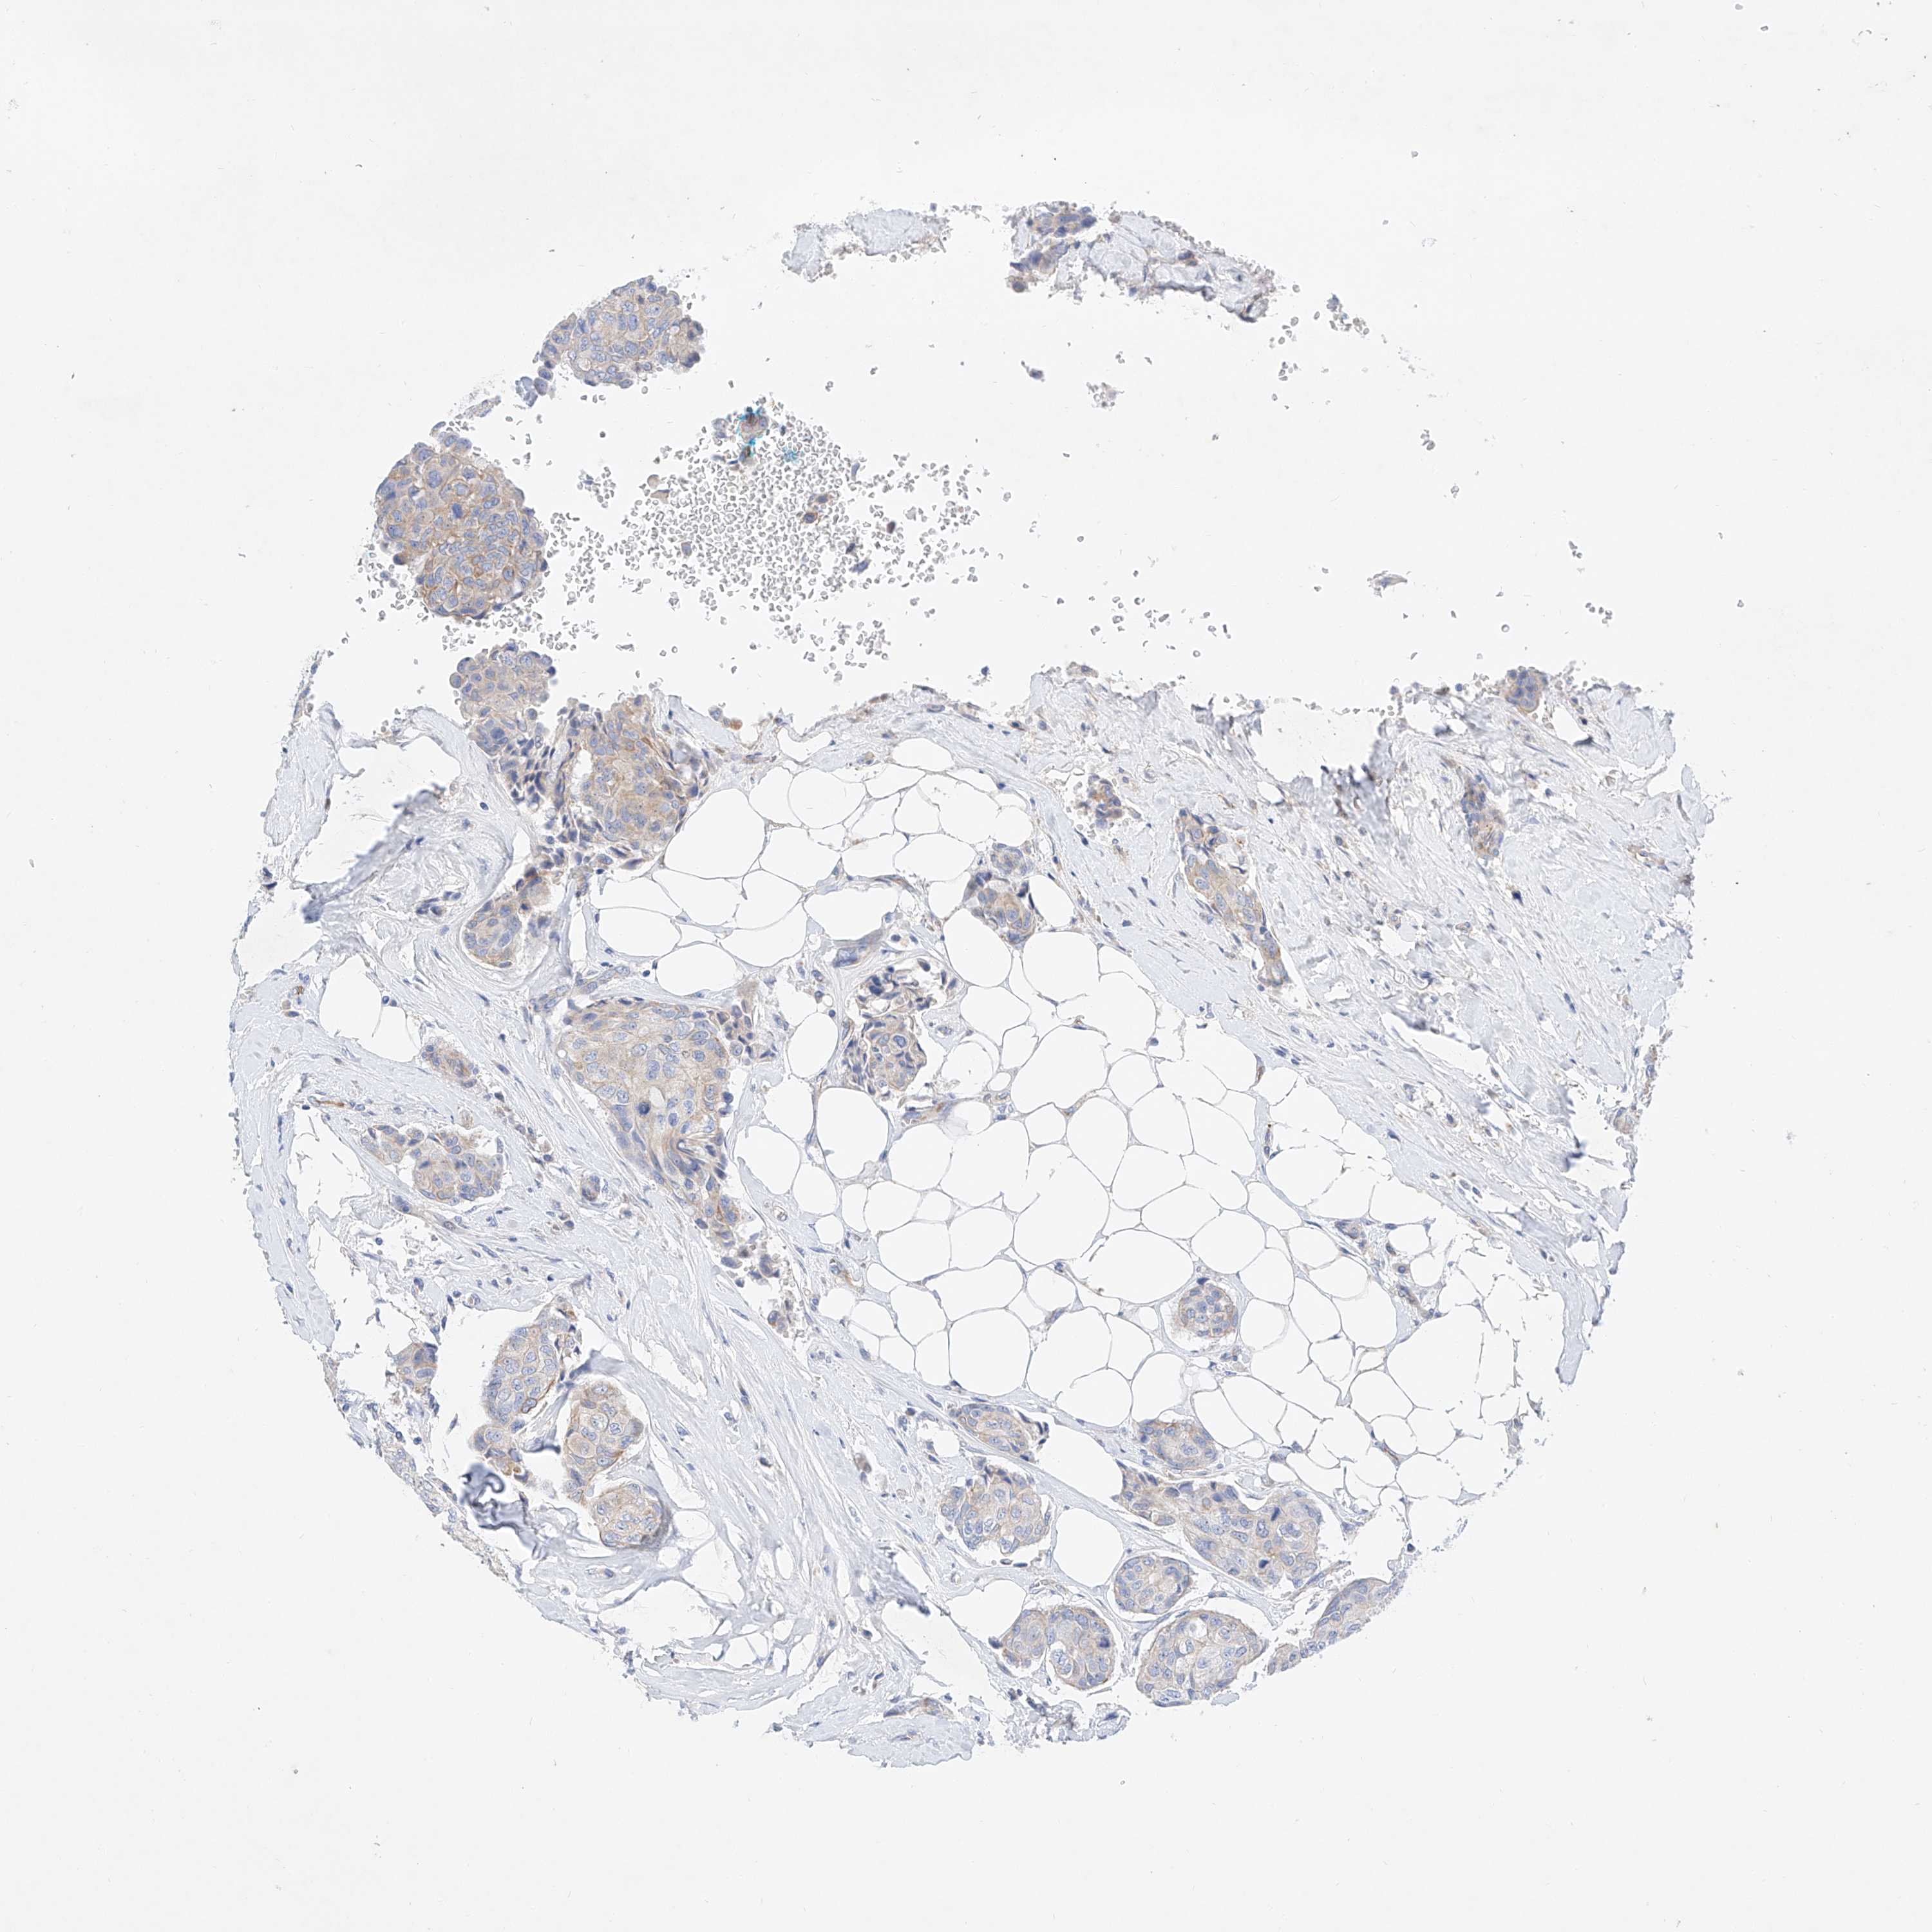

CANCER BREAST CANCER Show tissue menu

BRCA TCGA BRCA VALIDATION PROTEIN EXPRESSION

Breast cancer

Human cancer